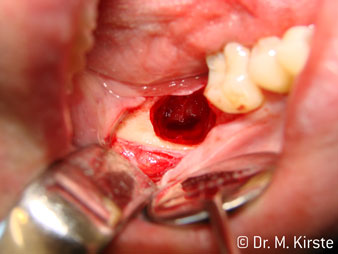

La scelta dell'angolo di 45° del contrangolo offre numerosi vantaggi in sede di utilizzo. I colleghi chirurghi, per i quali è stato messo a punto in primo luogo il contrangolo, noteranno in fretta la possibilità di lavorare in modo molto mirato. In particolare, durante l'estrazione dei denti del giudizio (Fig. 2), non sono necessarie estese resezioni del tessuto molle nell'area della guancia (Fig. 3). La forma della testina del contrangolo, insieme a lievi rotazioni della stessa durante la preparazione, permettono di lavorare in modo rapido e sicuro nella regione retromolare.

La concezione professionale del sistema di cuscinetti nel cuore della testina del contrangolo assicura un funzionamento silenzioso delle frese; durante l'estrazione di denti e radici (Fig. 4 - 9) si ottiene un taglio estremamente preciso e stabile.